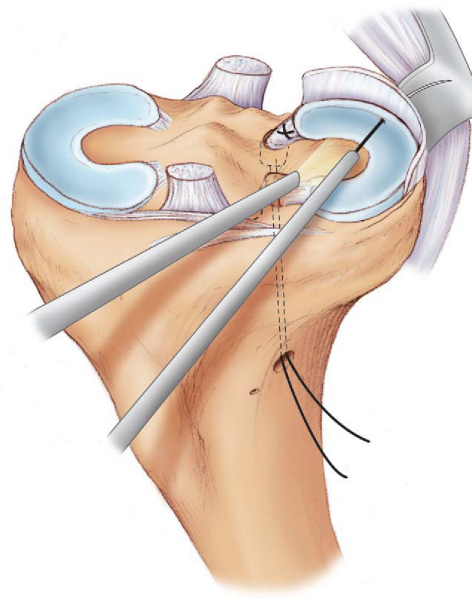

After completion of the meniscal bed preparation and notchplasty, the leg is exsanguinated and the tourniquet is adjusted to an appropriate pressure. A 5-cm anteromedial arthrotomy is made for graft passage, and a standard posterior medial approach for inside-out suture passage is made. The anteromedial arthrotomy should include the anteromedial portal and also incorporate the intended bone tunnel sites. With use of an anterior cruciate ligament guide set at the appropriate angle, a pin is inserted from adjacent to the tibial tubercle to the anatomic insertion site of the posterior horn of the medial meniscus under direct visualization (

Fig. 49-6

). The guide wire is then overreamed with a 10-mm reamer, and the tunnel edges are chamfered with a curved 4.5-mm shaver. A looped 20-gauge wire is advanced in the tibial tunnel in a retrograde fashion and retrieved out of the arthrotomy with a grasper (

Fig. 49-7

). The sutures in the posterior bone plug are then passed through the wire loop and retrieved through the tunnel. The graft is then passed through the arthrotomy and into the knee with the knee in 15 to 20 degrees of flexion and under a maximum valgus stress (

Fig. 49-8

). The meniscus is then reduced into position with direct pressure by use of a probe, a technique similar to the reduction of a bucket-handle meniscal tear. In some instances, this may require release of the superficial fibers of the medial collateral ligament for adequate clearance in the medial compartment. Once the meniscus is reduced, the posterior bone plug is seated in the tunnel with the aid of a probe and traction on the plug sutures. The posterior bone plug is purposely undersized by 2 mm for ease of passage at this stage. A snap is placed on the posterior bone plug suture limbs as they exit the distal tibial tunnel to maintain tension until the rest of the meniscus can be secured.

Figure 49-6 |

Figure 49-7 |

Figure 49-8 |